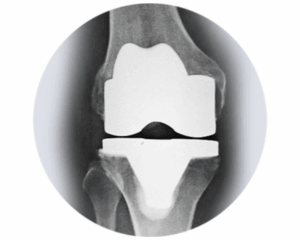

Sistema de rodilla primaria Freedom®

El sistema Freedom Primary Knee es la solución integral avanzada para la artroplastia total de rodilla que brinda a los pacientes un movimiento óptimo de alta flexión, hasta 155 grados.

La prótesis de rodilla Freedom Primary, con una base universal, está diseñada para imitar la función natural de la rodilla y está disponible en varios tamaños para componentes tibiales tanto de polietileno como con soporte metálico. Garantiza resultados predecibles y consistentes para el paciente tras un reemplazo total de rodilla primario.